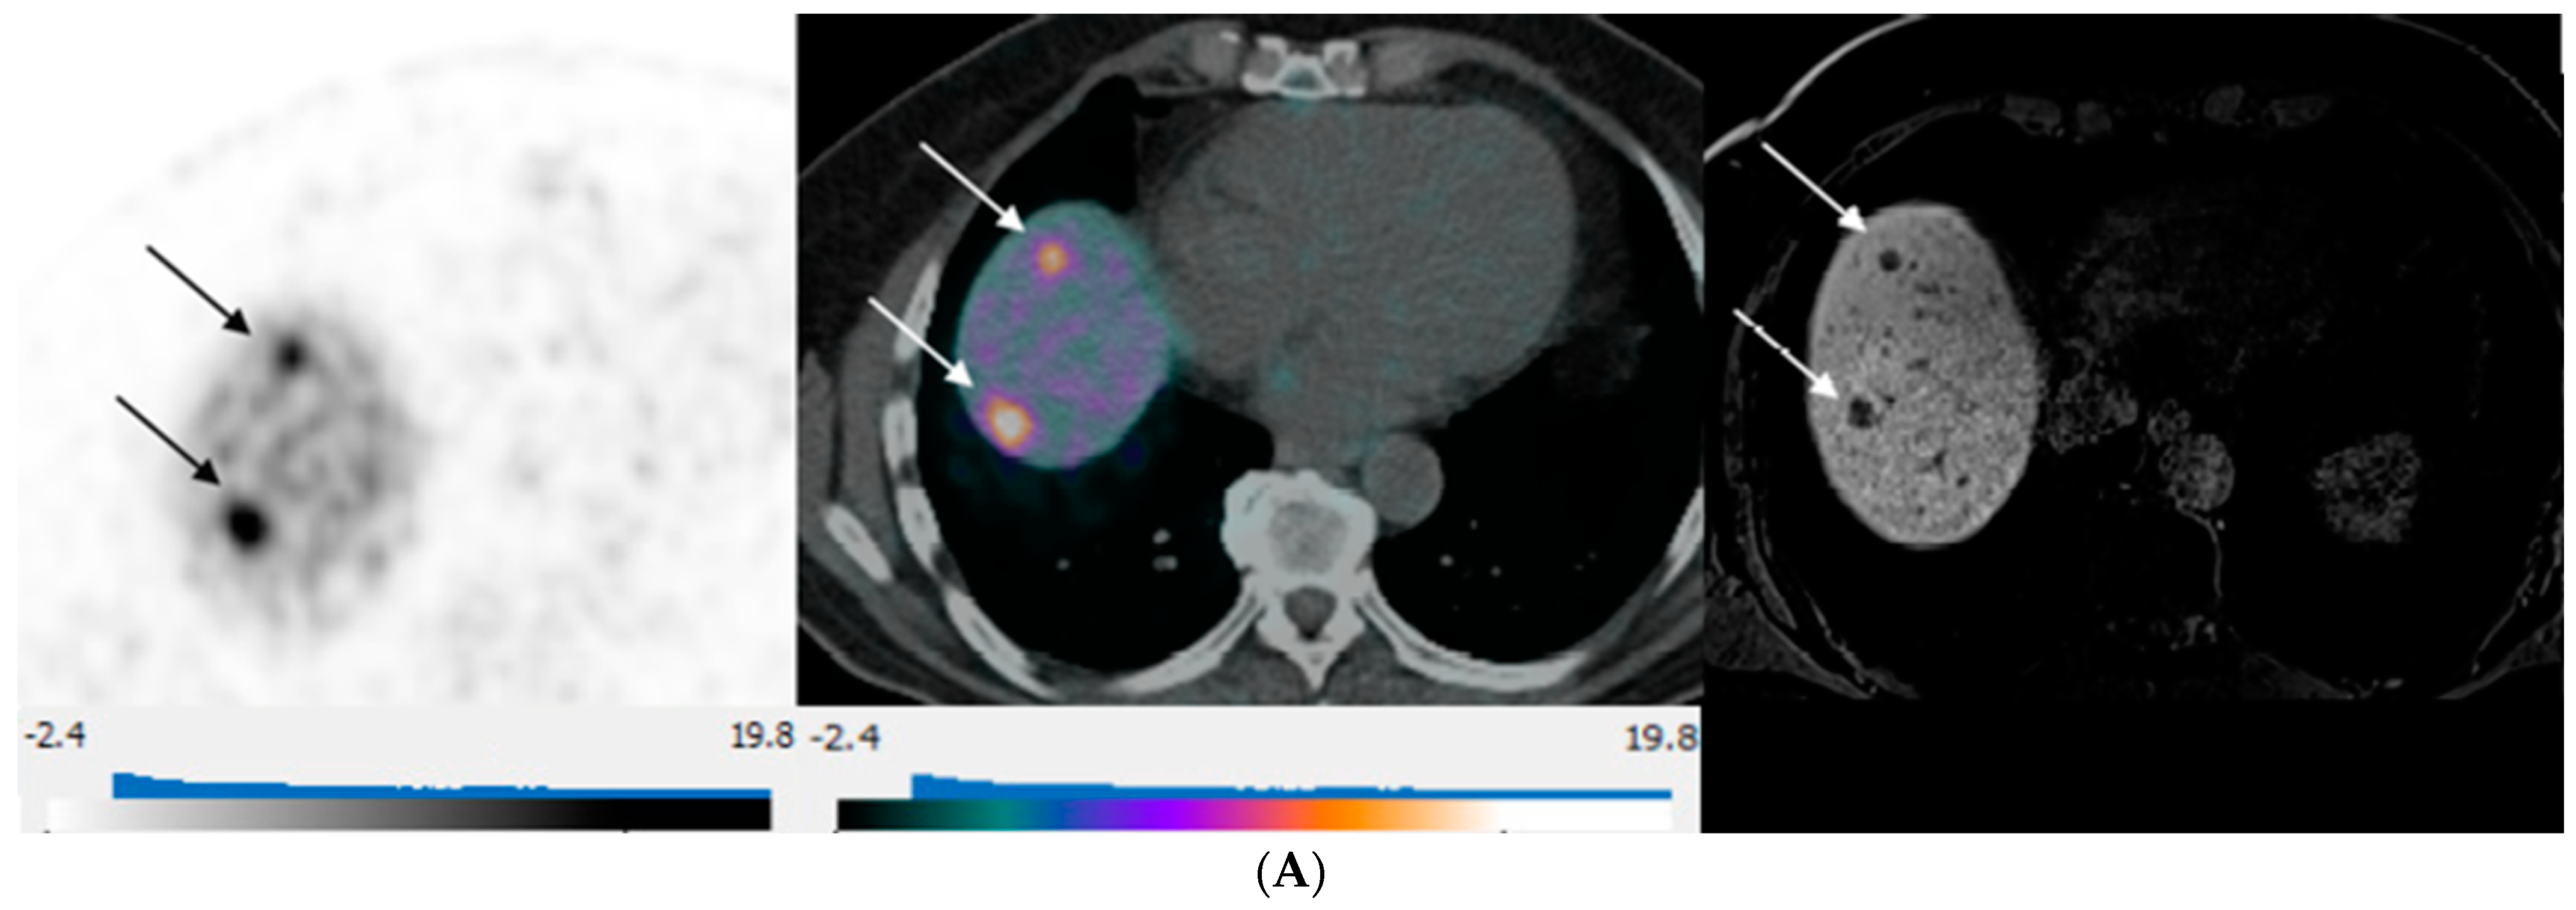

3. Results